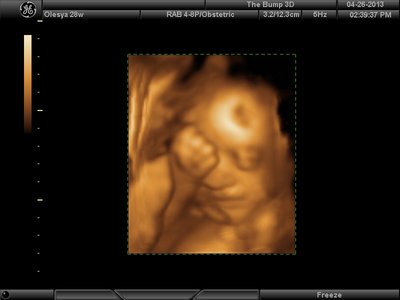

Еще одна, качество ужасное..

image.jpg [ 60.32 КБ | Просмотров: 1237 ]